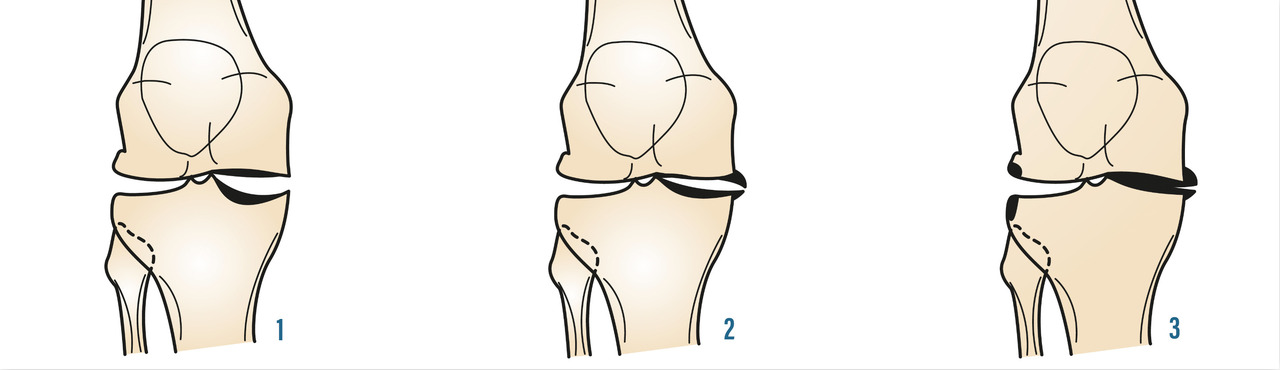

Là encore, de « simples » radiographies standard sont suffisantes et en aucun cas une IRM ou un scanner du genou ne doit être demandé en première intention. L’examen se fait de face et de profil, en appui bipodal, en rotation nulle, le genou en extension et avec un défilé fémoro-patellaire à 30° de flexion. Un examen en « schuss » (face, en charge, 30° de flexion) peut aussi être demandé. On y recherche un pincement fémoro-tibial interne ou externe, ainsi que des ostéophytes marginaux. On recherche sur le profil une ostéophytose située en avant et en arrière du tibia, ainsi que sur les condyles fémoraux. Il peut également exister une ostéocondensation sous-chondrale et des géodes dans les compartiments atteints (fig. 3 et 4).